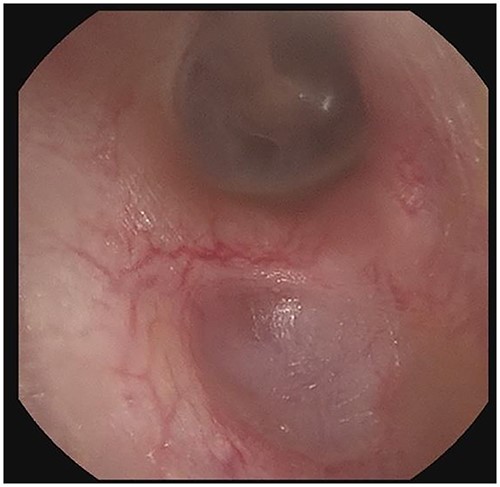

Right external auditory canal on patient A demonstrating excellent mucosalization of the indentation in the inferior aspect of the external auditory canal after serial cerumen debridement procedures in the office.

The patient evaluation and the data collection of this rare entity were performed in the senior author’s Otolaryngology practice in Poplar Bluff Regional Medical Center, Poplar Bluff, Missouri, USA (Table 1). Patient A, a 72-year-old female, was initially seen in 06/2015 and has been consistently followed for 87 months. On initial evaluation, the unusual clinical presentation triggered a workup with a CT of the temporal bone (Fig. 1), revealing a minor area of cortical erosion in the inferior wall of her right bony external auditory canal. Her initial presenting complaint was cerumen impaction on the right side associated with same side hearing loss. The patient has no history of diabetes, is treated with estradiol and progesterone tablets for hormonal replacement therapy and has no diagnosis of osteoporosis. Her blood pressure medications include atenonol and triamteren and has been on the same medications for the last seven years of our observation. The patient was managed with serial external auditory canal debridements, every 6 months. She had no history of otitis externa during the years of follow-up. Photographic documentation in her most recent visit (10/2022) revealed healthy appearing healthy mucosalization of the cavity and minimal amount of ceruminous debris (Fig. 2).